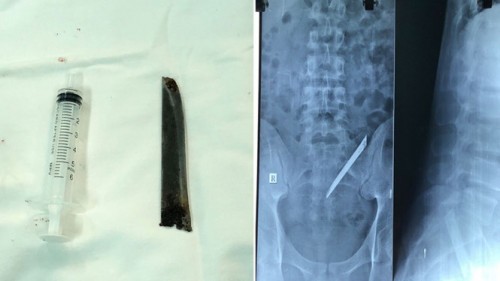

ưỡi dao Thái Lan trong cơ thể bệnh nhân trên phim X-quang và lưỡi dao khi được lấy ra.

Ngày 15/12, bác sĩ chuyên khoa 2 Nguyễn Quang Huy, Trưởng Khoa ngoại tổng quát, Bệnh viện (BV) Nhân dân 115 (TP.HCM) cho biết, bệnh viện đã thực hiện phẫu thuật lấy lưỡi dao Thái Lan dài khoảng 12 cm ra khỏi cơ thể nam bệnh nhân N.H.L. (24 tuổi, ngụ Q.6, TP.HCM).

Sau 1h30 phẫu thuật, các bác sĩ đã lấy ra dị vật là một lưỡi dao Thái Lan dai khoảng 12 cm. May mắn cho bệnh nhân là lưỡi dao không làm tổn thương các rễ thần kinh, chỉ tổn thương các cơ và bao xơ cạnh cột sống. Sau phẫu thuật, sức khỏe anh L. đang dần ổn định.